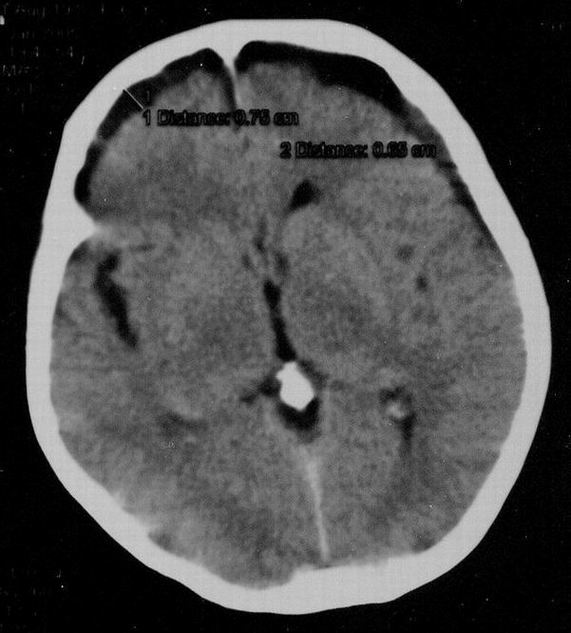

Медицинские аспекты и диагностика субдуральной гигромы мозга